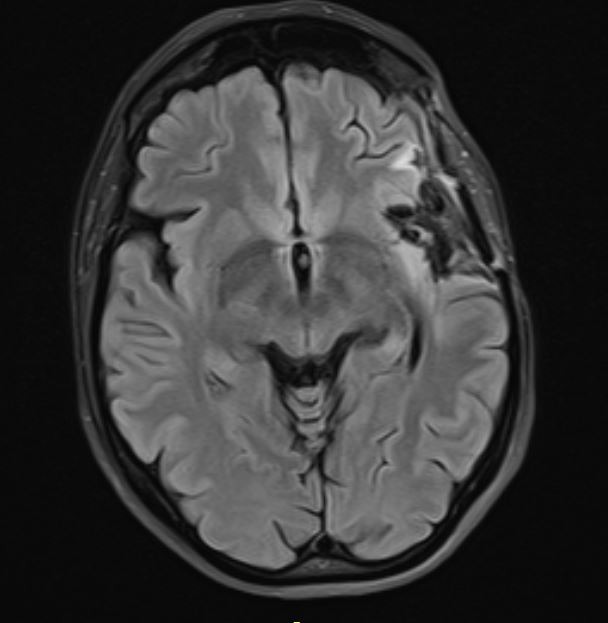

Ο έλεγχος με μαγνητική έδειξε όγκο στο αριστερό ημισφάιριο, σε δύσκολο σημείο, τόσο λειτουργικά όσο και χειρουργικά.

Η μετεγχειρητική μαγνητική τομογραφία ανέδειξε πλήρη εξαίρεση του όγκου.